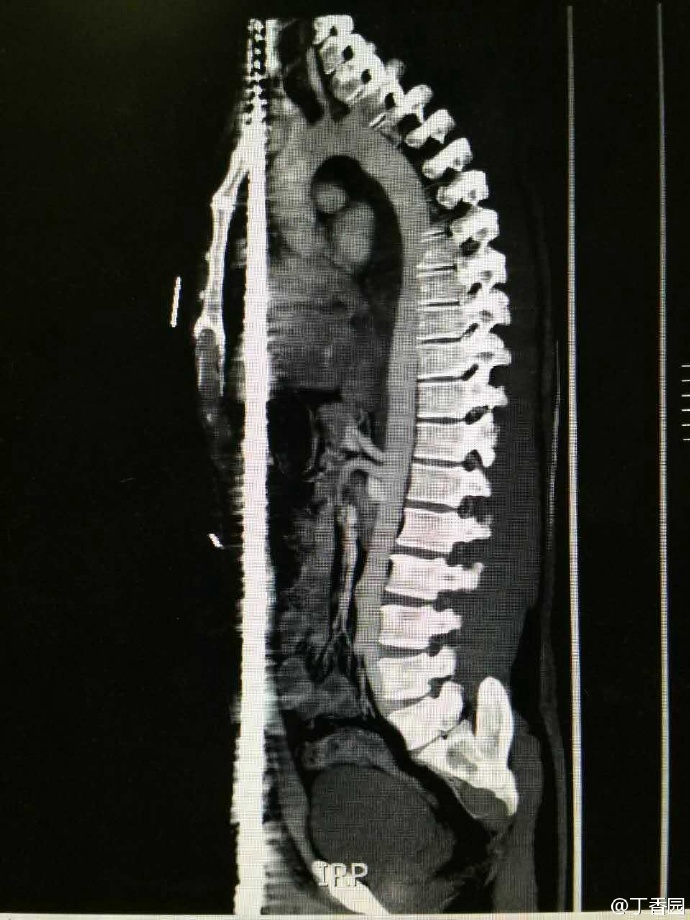

齐鲁医院的病例——正中贯通伤

004.jpg (216.02 KB)

004.jpg

真命大